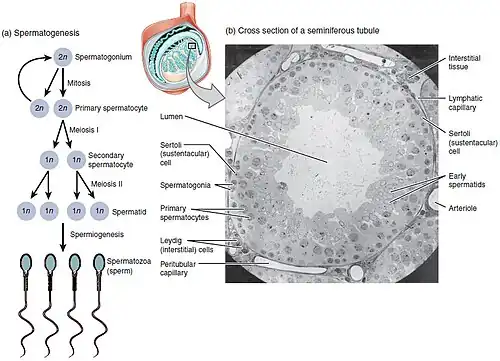

Spermatogenesis is the process by which haploid spermatozoa develop from germ cells in the seminiferous tubules of the testicle. This process starts with the mitotic division of the stem cells located close to the basement membrane of the tubules.[1] These cells are called spermatogonial stem cells. The mitotic division of these produces two types of cells. Type A cells replenish the stem cells, and type B cells differentiate into primary spermatocytes. The primary spermatocyte divides meiotically (Meiosis I) into two secondary spermatocytes; each secondary spermatocyte divides into two equal haploid spermatids by Meiosis II. The spermatids are transformed into spermatozoa (sperm) by the process of spermiogenesis. These develop into mature spermatozoa, also known as sperm cells.[2] Thus, the primary spermatocyte gives rise to two cells, the secondary spermatocytes, and the two secondary spermatocytes by their subdivision produce four spermatozoa and four haploid cells.[3]

Spermatogenesis starts in the bottom part of seminiferous tubes and, progressively, cells go deeper into tubes and moving along it until mature spermatozoa reaches the lumen, where mature spermatozoa are deposited. The division happens asynchronically; if the tube is cut transversally one could observe different maturation states. A group of cells with different maturation states that are being generated at the same time is called a spermatogenic wave.[5]

Spermatocytogenesis

Spermatocytogenesis is the male form of gametocytogenesis and results in the formation of spermatocytes possessing half the normal complement of genetic material. In spermatocytogenesis, a diploid spermatogonium, which resides in the basal compartment of the seminiferous tubules, divides mitotically, producing two diploid intermediate cells called primary spermatocytes. Each primary spermatocyte then moves into the adluminal compartment of the seminiferous tubules and duplicates its DNA and subsequently undergoes meiosis I to produce two haploid secondary spermatocytes, which will later divide once more into haploid spermatids. This division implicates sources of genetic variation, such as random inclusion of either parental chromosomes, and chromosomal crossover that increases the genetic variability of the gamete. The DNA damage response (DDR) machinery plays an important role in spermatogenesis. The protein FMRP binds to meiotic chromosomes and regulates the dynamics of the DDR machinery during spermatogenesis.[13] FMRP appears to be necessary for the repair of DNA damage.

Spermatidogenesis

Spermatidogenesis is the creation of spermatids from secondary spermatocytes. Secondary spermatocytes produced earlier rapidly enter meiosis II and divide to produce haploid spermatids. The brevity of this stage means that secondary spermatocytes are rarely seen in histological studies.

Spermiogenesis

During spermiogenesis, the spermatids begin to form a tail by growing microtubules on one of the centrioles, which turns into basal body. These microtubules form an axoneme. Later the centriole is modified in the process of centrosome reduction.[16] The anterior part of the tail (called midpiece) thickens because mitochondria are arranged around the axoneme to ensure energy supply. Spermatid DNA also undergoes packaging, becoming highly condensed. The DNA is packaged firstly with specific nuclear basic proteins, which are subsequently replaced with protamines during spermatid elongation. The resultant tightly packed chromatin is transcriptionally inactive. The Golgi apparatus surrounds the now condensed nucleus, becoming the acrosome.

Maturation then takes place under the influence of testosterone, which removes the remaining unnecessary cytoplasm and organelles. The excess cytoplasm, known as residual bodies, is phagocytosed by surrounding Sertoli cells in the testes. The resulting spermatozoa are now mature but lack motility. The mature spermatozoa are released from the protective Sertoli cells into the lumen of the seminiferous tubule in a process called spermiation.

Role of Sertoli cells

At all stages of differentiation, the spermatogenic cells are in close contact with Sertoli cells which are thought to provide structural and metabolic support to the developing sperm cells. A single Sertoli cell extends from the basement membrane to the lumen of the seminiferous tubule, although the cytoplasmic processes are difficult to distinguish at the light microscopic level.